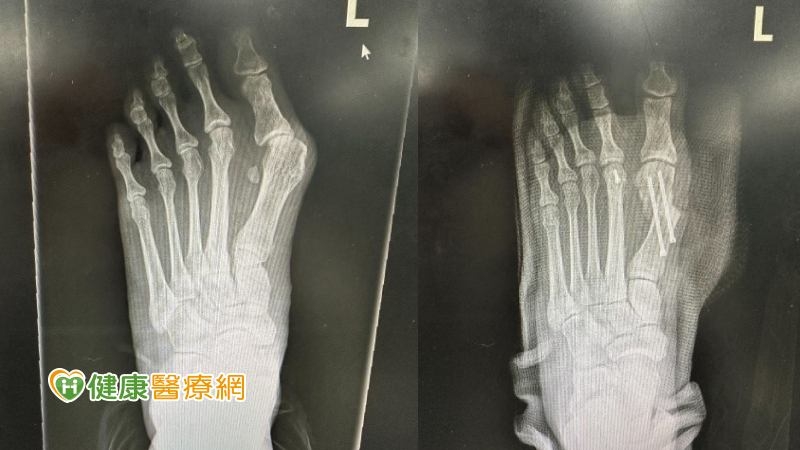

【健康醫療網/記者吳儀文報導】張小姐因工作關係每天需要穿著高跟鞋,大拇指內側長期與鞋面摩擦,半年前開始無法久站,走路不到半小時,腳底就痛到像火在燒,拇指呈現ㄑ字型根部又凸又腫,就醫檢查時拇趾已外翻將近40度。

「拇趾外翻」的患者腳背第一掌骨與大拇趾間的關節會呈現外凸彎曲。陳建樺醫師提到,拇指外翻常會伴隨其餘腳趾的擠壓變形、足部疼痛外翻,外觀上大拇趾會往第二拇趾偏移15度以上,使大拇趾、第二拇趾交疊,使第二拇趾異位,導致穿鞋時摩擦不適,大拇趾根部的骨頭突出且紅腫發痛。

陳建樺醫師表示,拇趾外翻初期可以先透過消炎止痛藥、改善穿鞋習慣,減輕病情惡化,不過無法根治外翻,當保守治療一段時間後疼痛感仍未緩解,病人可以考慮接受大腳趾外翻手術,矯正腳趾變形並重整腳趾平衡。